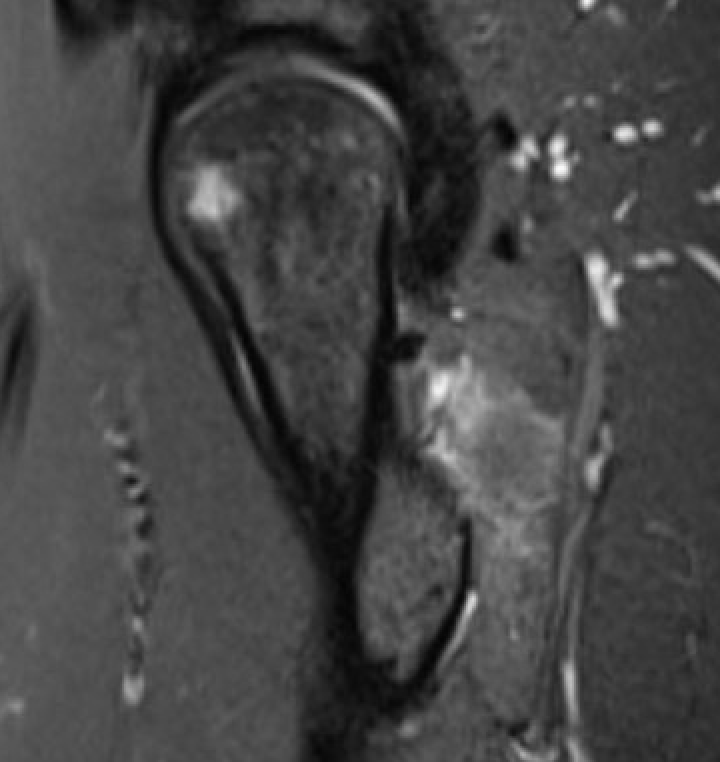

MRI

Reduced ischiofemoral space - distance between the lesser trochanter and the ischial tuberosity

Reduced quadratus femoris space - distance between hamstring tendon and iliopsoas

Inflammation / edema in quadratus femoris +/- fatty degeneration

IFIIFI

IFIIFIIFI